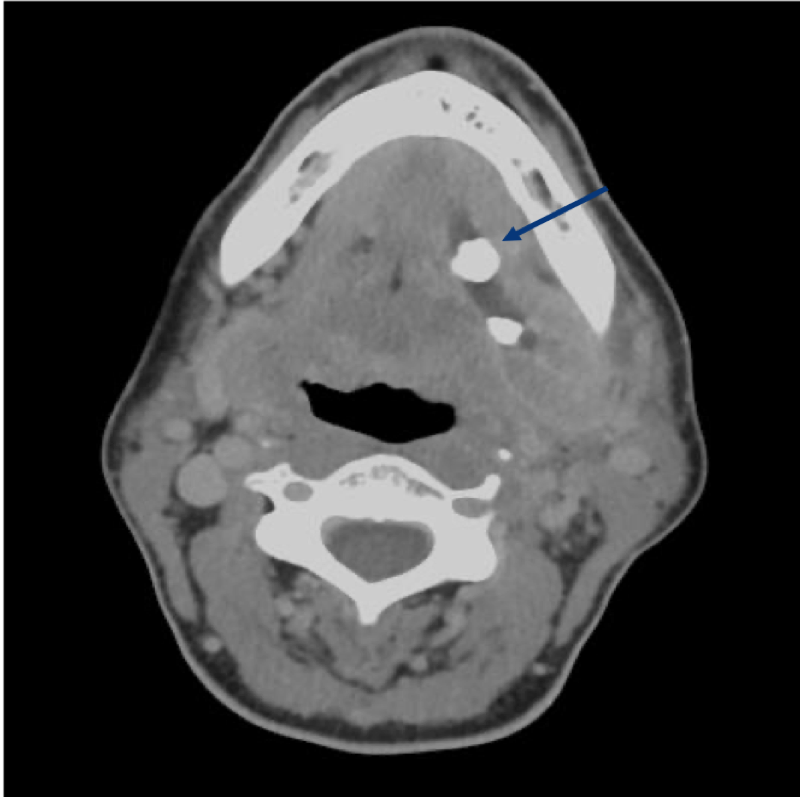

- les lithiases (calculs) salivaires, principalement au niveau de la glande sub-mandibulaire située dans le cou ;

La chirurgie des lithiases concerne donc principalement la glande sub-mandibulaire. Elle consiste à retirer le calcul électivement par voie orale ou bien toute la glande si nécessaire.

Avant l’intervention chirurgicale, vous devez consulter votre chirurgien muni d’un bilan d’imagerie, si tel n’est pas le cas, il sera prescrit lors de la première consultation (panoramique dentaire et échographie cervicale si suspicion de lithiase/ TDM cervico-faciale et IRM parotidienne si suspicion de tumeur). Votre chirurgien décidera en fonction de la pathologie suspectée et du bilan d’imagerie, l’indication d’exérèse et son caractère plus ou moins urgent. Une consultation pré anesthésique est obligatoire en cas d’anesthésie générale ou de neuroleptanalgésie (anesthésie semi profonde sans intubation associée à une anesthésie locale).